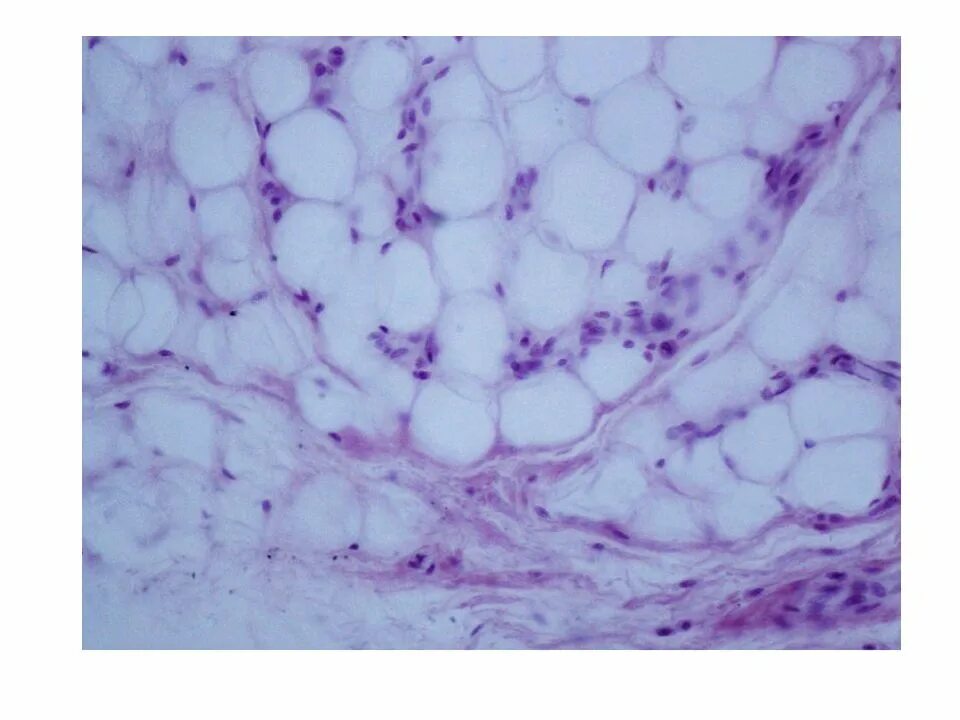

Гистологические препараты соединительная ткань